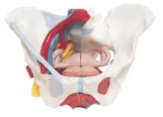

Body Organ Models

Human Organ Models provide an accurate three-dimensional replica of the human anatomy that's used for medical education and training. Manufacturer 3B Scientific is a world leader in high-quality human internal organ models. Both realistic and colorful, these models help students learn anatomical structures and common abnormalities.

Without access to an anatomical model, structures may be covered up or too small to learn with the naked eye. Models are essential to learning and present different angles while key structures and functions are explored. The Kidney Section is a cross-section replica that is three-times life-size to provide an internal view of its framework that would be impossible to see in a cadaver. A MICROanatomy Kidney is another variation to further magnify the individual zones of the kidney.

Whether students are learning about the skin, the biggest organ of the body, or learning about the digestive system, 3B has the model to facilitate learning about the 12 human organ systems.